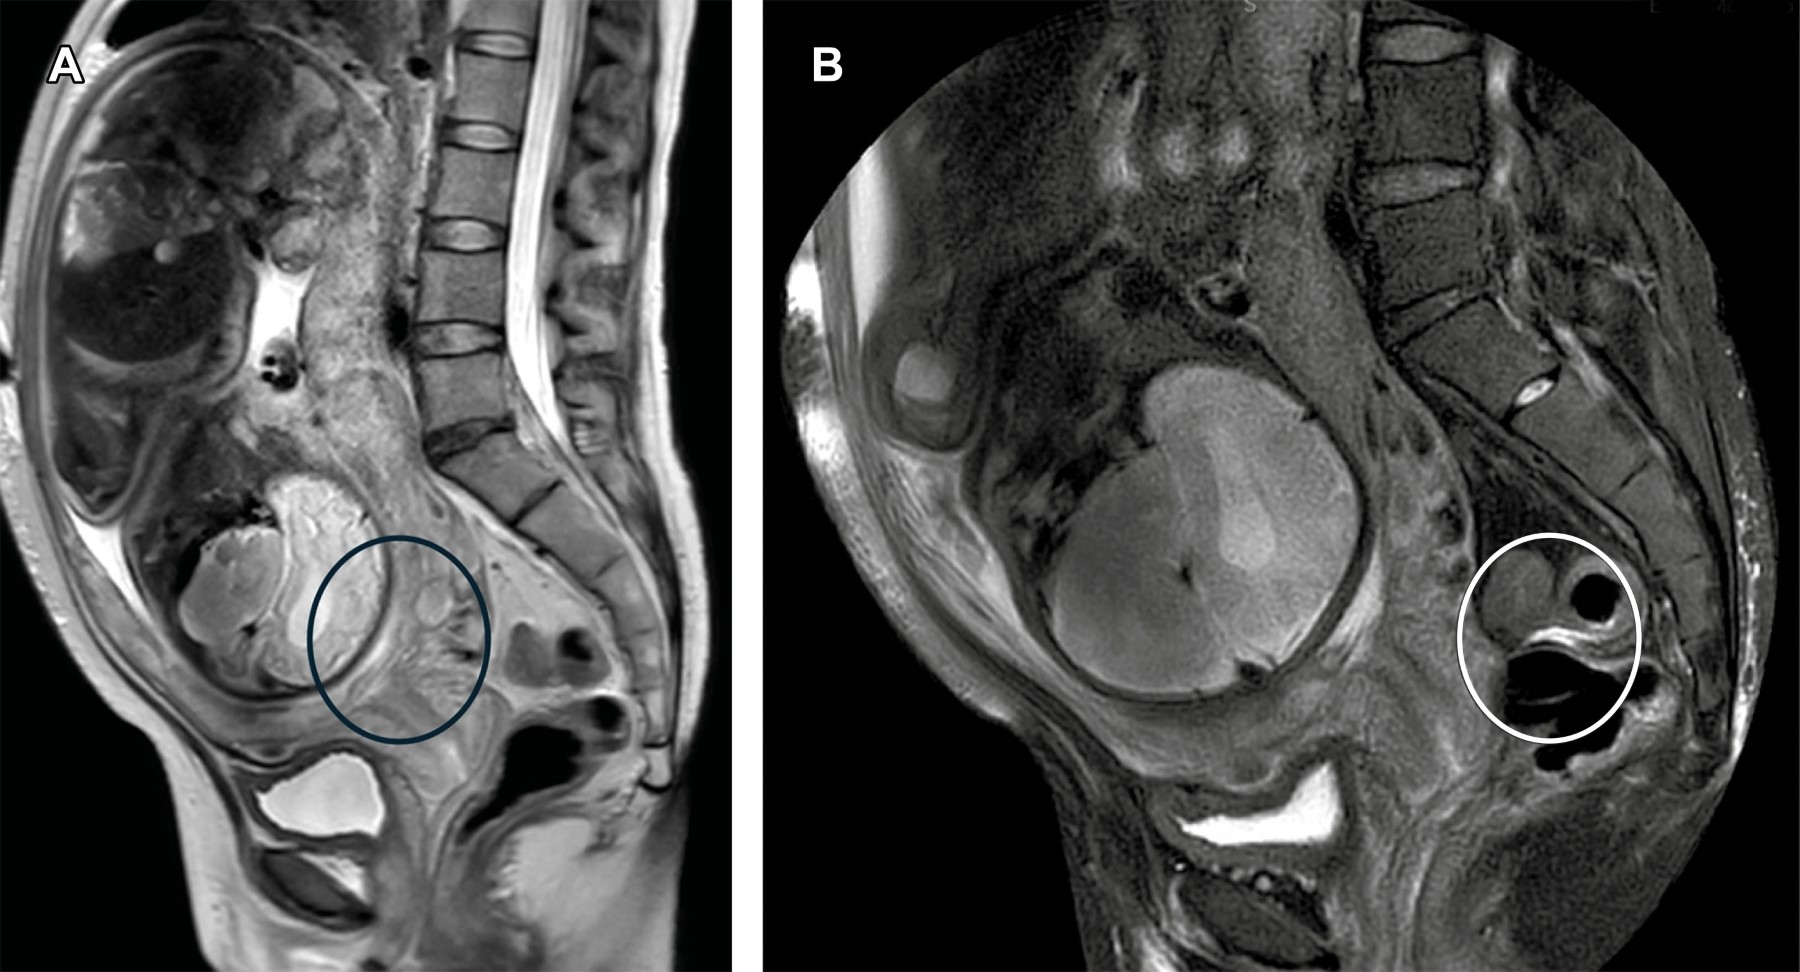

Las características por imagen en RM son: bandas oscuras interplanetarias en T2, pérdida de la línea retroplacentaria, vascularización anormal del lecho placentario, abultamiento uterino-placentario, adelgazamiento del miometrio, masa exofítica focal e interrupción de la pared de la vejiga (Tabla 1),1 dichos hallazgos se ejemplifican en las Figuras 1 y 2 en donde se identifica la placenta de bordes lobulados, heteroge?nea, con zonas lineales y otras puntiformes de baja sen?al en su interior. Coexisten zonas de pe?rdida de la interfase con el miometrio, así como localización de la placenta hacia el borde inferior del orificio del cervical interno.

Figura 2